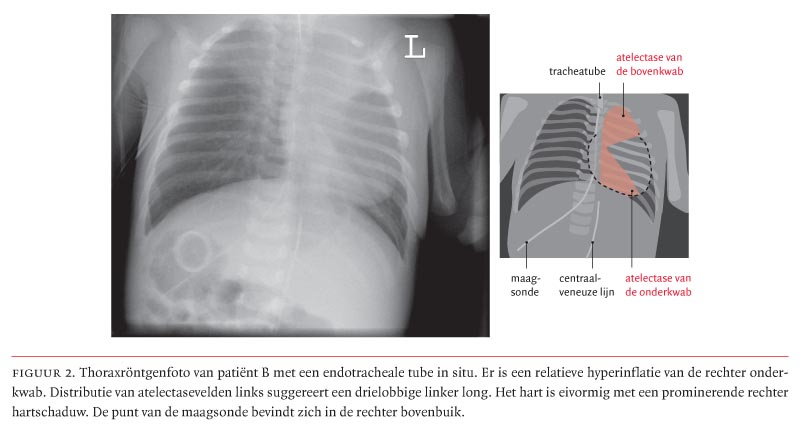

Omdat werd gedacht aan een cor vitium met afhankelijkheid van de ductus arteriosus (Botalli), werd intraveneus prostaglandine-E1 gegeven om de ductus open te houden. Dit gaf echter geen verbetering van de saturatie. De patiënt werd daarop geïntubeerd en beademd. De thoraxfoto na intubatie toonde naast de reeds genoemde bevindingen een relatieve hyperinflatie van de rechter onderkwab met een atelectase links, suggestief voor een drielobbige linker long (figuur 2). Met echocardiografie werd inderdaad een ductusafhankelijk cor vitium vastgesteld met situs inversus van de atria en de ventrikels. Echografisch onderzoek van het abdomen bevestigde de situs inversus van de buikorganen. Patiënt had derhalve een situs inversus totalis.